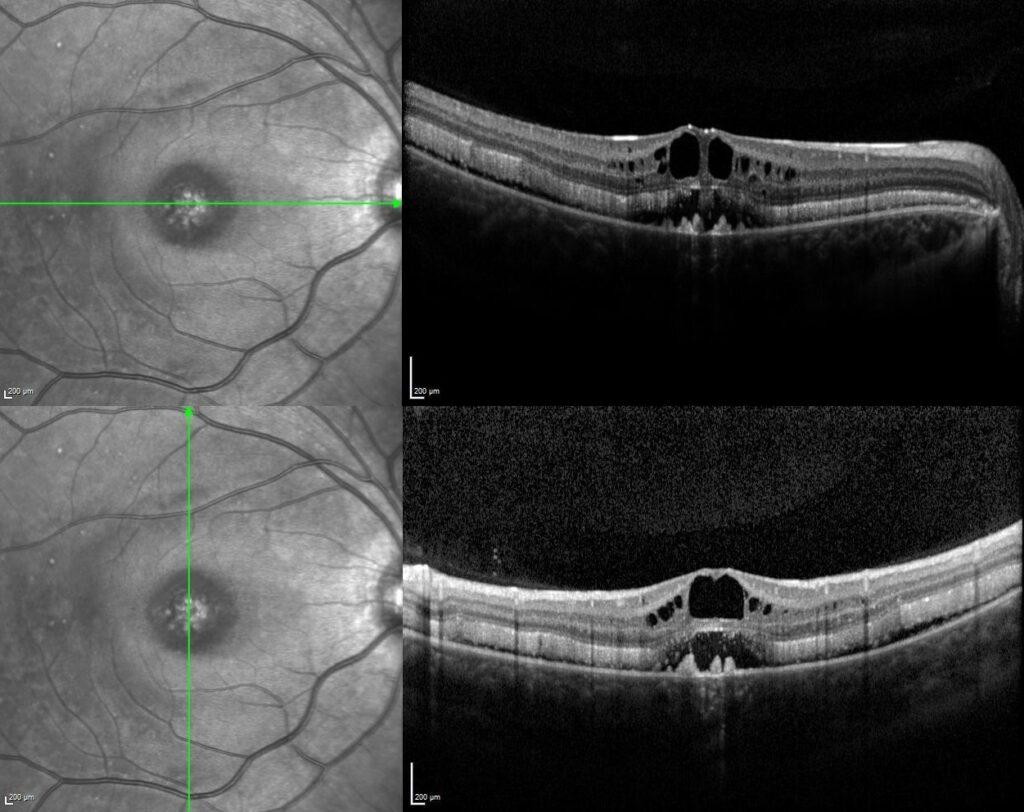

Vertical and horizontal optical coherence tomography scans passing through the fovea revealed serous retinal detachment, retinoschisis with intraretinal cysts, brush border appearance caused by elongation of the outer segments of photoreceptors, and hyperreflective dome-shaped deposits at the level of retinal pigment epithelium in both eyes.